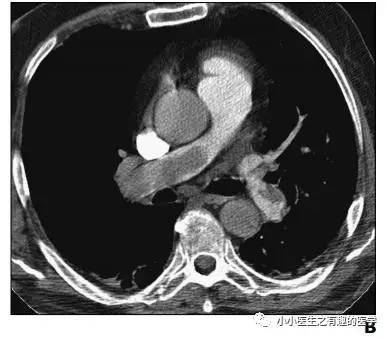

没看够?再来一个,让你一次看个够。

不光是肺栓塞,连主动脉夹层,都发现了。牛。我来标记一下。